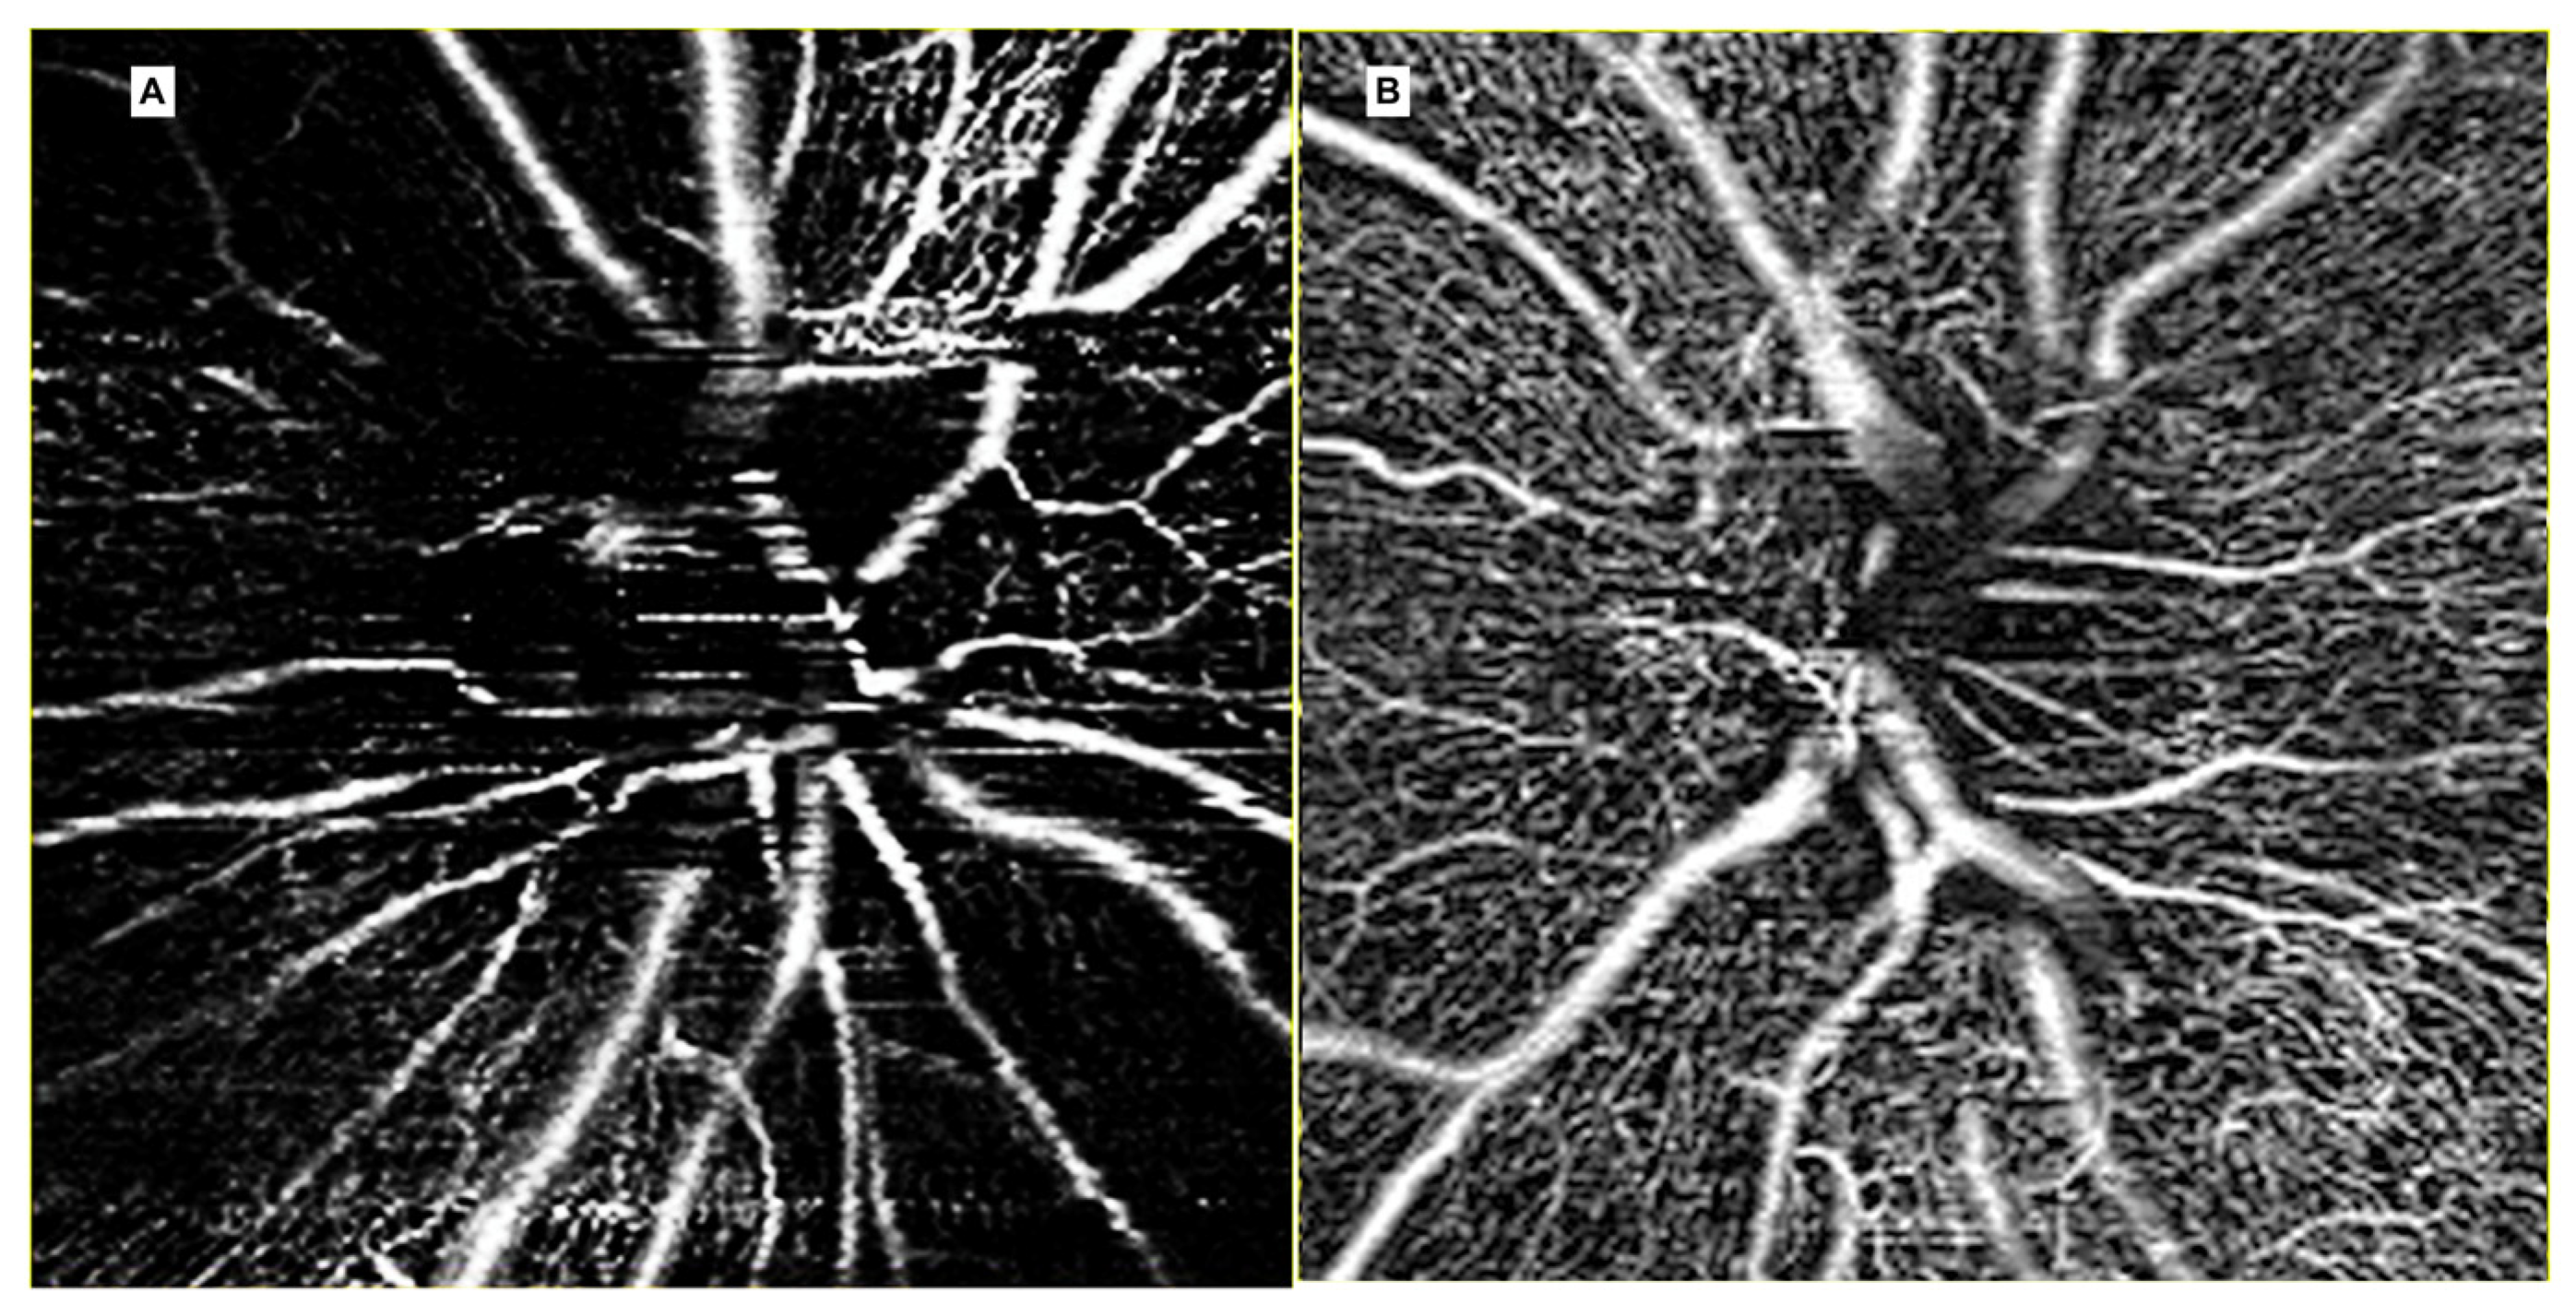

3.3. Radiation Optic Neuropathy

- Parrozzani, R.; Leonardi, F.; Frizziero, L.; Trevisson, E.; Clementi, M.; Pilotto, E.; Fusetti, S.; Miglionico, G.; Midena, E. Retinal Vascular and Neural Remodeling Secondary to Optic Nerve Axonal Degeneration: A Study Using OCT Angiography. Ophthalmol. Retin 2018, 2, 827–835. [Google Scholar] [CrossRef]

- Skalet, A.H.; Liu, L.; Binder, C.; Miller, A.K.; Wang, J.; Wilson, D.J.; Crilly, R.; Thomas, C.R.; Hung, A.Y.; Huang, D.; et al. Quantitative OCT Angiography Evaluation of Peripapillary Retinal Circulation after Plaque Brachytherapy. Ophthalmol. Retin 2018, 2, 244–250. [Google Scholar] [CrossRef]

| Grade 0 | - Regular radial distribution of the peripapillary capillaries - Absence of vessels abnormalities |

| Grade 1 * | - Loss of the radial pattern of the RPCP - Absence of peripapillary ischemia |

| Grade 2 * | - Peripapillary hypoperfusion in less than two quadrants (defined area of RPCP dropout) |

| Grade 3 * | - Peripapillary hypoperfusion in more than two quadrants (RPCP dropout > 180°) |

| Grade 4 † | - Peripapillary hypoperfusion, (complete RPCP dropout or poor OCT image quality) |